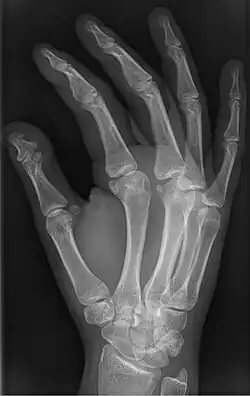

Brachyphalangy is a condition in which one or more of the phalanges of the fingers and toes are smaller than normal.[1]

This condition is one of the most common non-syndromic causes of brachydactyly and clinodactyly.

This condition is caused by either fusion or early closure of the phalange's growth plate. One example is brachydactyly type D, which is caused by an early closure of the thumb's distal phalange, leading to a congenitally short thumb with a similarly short and wide thumb nail.